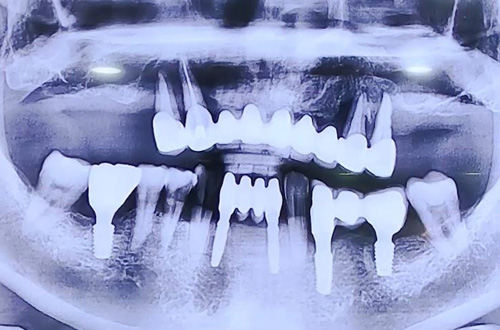

윗니 전체 임플란트 사례

22-11-23 더365치과

AFTER

따라서 당일 윗니 전체 임플란트를 진행하시고

임시틀니까지 바로 만들어 치아의 형태를 가지고 귀가하실 수 있도록 하는 것을 목표했는데요.

임플란트를 위해 기존 치아를 빼면서 즉시 본원의 3D 스캐너 트리오스로 스캔 후 본을 뜨고

그 정보를 기공소로 전달해 임플란트 치료 중 실시간으로 틀니가 제작되도록 할 수 있답니다 ^^

윗니 전체 임플란트 후 예쁘게 제작된 임시틀니까지 장착해 마무리해 드렸는데요.

추후 임플란트가 충분히 굳고 나면 최종 보철로 완성해 드릴 계획입니다.